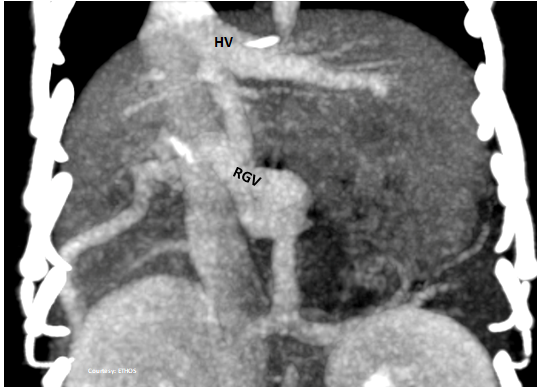

Does the RIGHT GASTRIC VEIN (RGV) contribute blood to the shunt?

WEISSE 2022

slide11